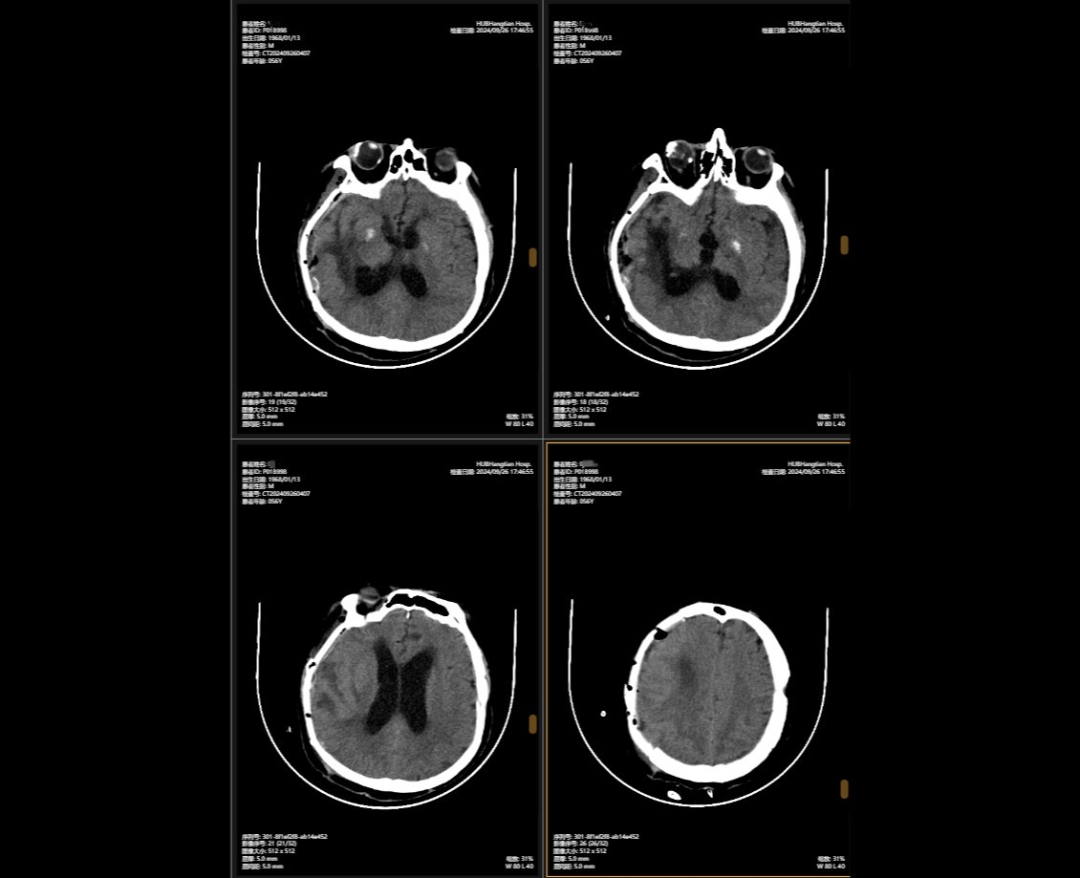

2024年5月,56歲的李先生(化名)不幸遭遇嚴(yán)重車禍,當(dāng)場昏迷,生命垂危。他被緊急送往湖北航天醫(yī)院后,檢查結(jié)果讓所有人心頭一緊:他的頭部受到嚴(yán)重撞擊,不僅有多處出血,腦組織也有挫傷,甚至連呼吸心跳的“總司令部”——腦干都受了傷。除此之外,還有顱骨、頸椎和多處肋骨骨折,情況萬分危急。

李先生頭部的多處損傷就像一顆顆“炸彈”,隨時可能危及生命。航醫(yī)神經(jīng)外科團(tuán)隊接診后,面對如此復(fù)雜的顱內(nèi)損傷,神經(jīng)外科主任陳義勇當(dāng)機(jī)立斷,一方面做好周密的手術(shù)準(zhǔn)備,一方面迅速展開多學(xué)科會診,多學(xué)科團(tuán)隊緊急集合,反復(fù)協(xié)商探討,一同制定了詳盡手術(shù)方案。手術(shù)方案確認(rèn)后,神外團(tuán)隊爭分奪秒,第一時間為李先生實施了顱內(nèi)多發(fā)血腫清除術(shù)+右側(cè)開顱顱內(nèi)減壓+去骨瓣減壓術(shù)+左側(cè)硬膜外血腫清除術(shù)+矢狀竇破裂止血術(shù)。手術(shù)過程中,醫(yī)生們精準(zhǔn)操作,成功止住了出血,最大限度地保護(hù)了正常腦組織,為李先生贏得了生的希望。

顱骨缺損修補術(shù)前術(shù)后對比